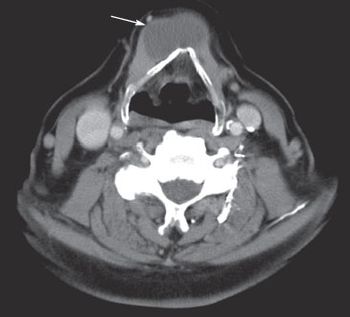

Thyroglossal duct cyst; HCV-HIV coinfection; slurred speech and trouble swallowing and chewing . . . see how well you do on the quiz questions this week.

For several years, an asymptomatic, firm, nontender mass had been growing on the neck of a 54-year-old-man, slightly left of midline at the level of the hyoid bone. Thyroid function tests were normal. What does it indicate?